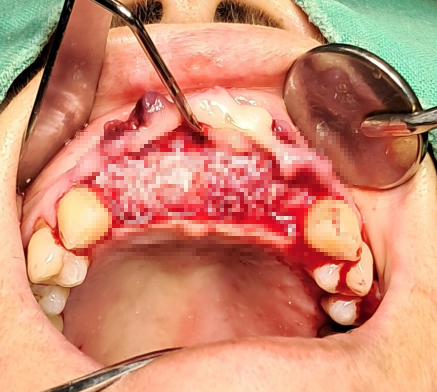

봉합 및 초기 회복 평가

수술 후에는

임플란트 고정 상태보다 연조직 반응과 봉합 안정성을 우선적으로 평가하였다.

* 봉합부 긴장도

* 혈류 반응

* 초기 염증 반응 여부

본 증례의 치료 목표는

“식립 완료”가 아니라

“안정적으로 회복될 수 있는 조건을 만드는 것”이었다.